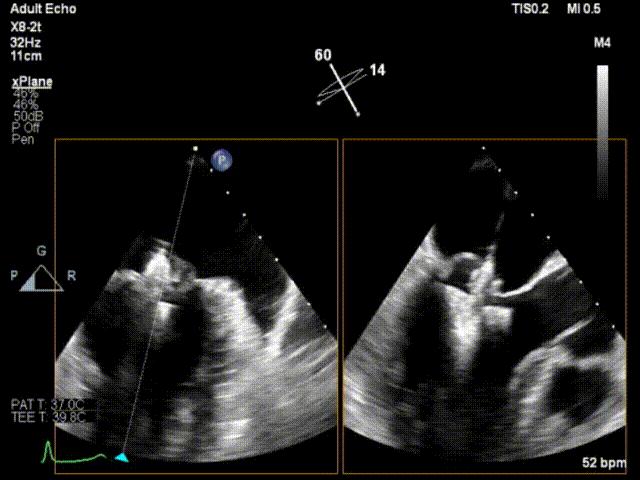

手术运用DSA与三维经食道超声心动图监测,通过患者股静脉穿刺房间隔途径建立夹合器输送轨道,将夹合器送进左心房,借助夹合器输送系统通过病变的二尖瓣部位,在心脏不停跳的状态下快速完成二尖瓣脱垂瓣叶的破获和夹合,夹合位置满意,超声提示反流降至1+,遂释放夹合器,反流最终程度为1+,结束手术,手术过程耗时一小时左右。

术中瓣叶捕获

释放夹子